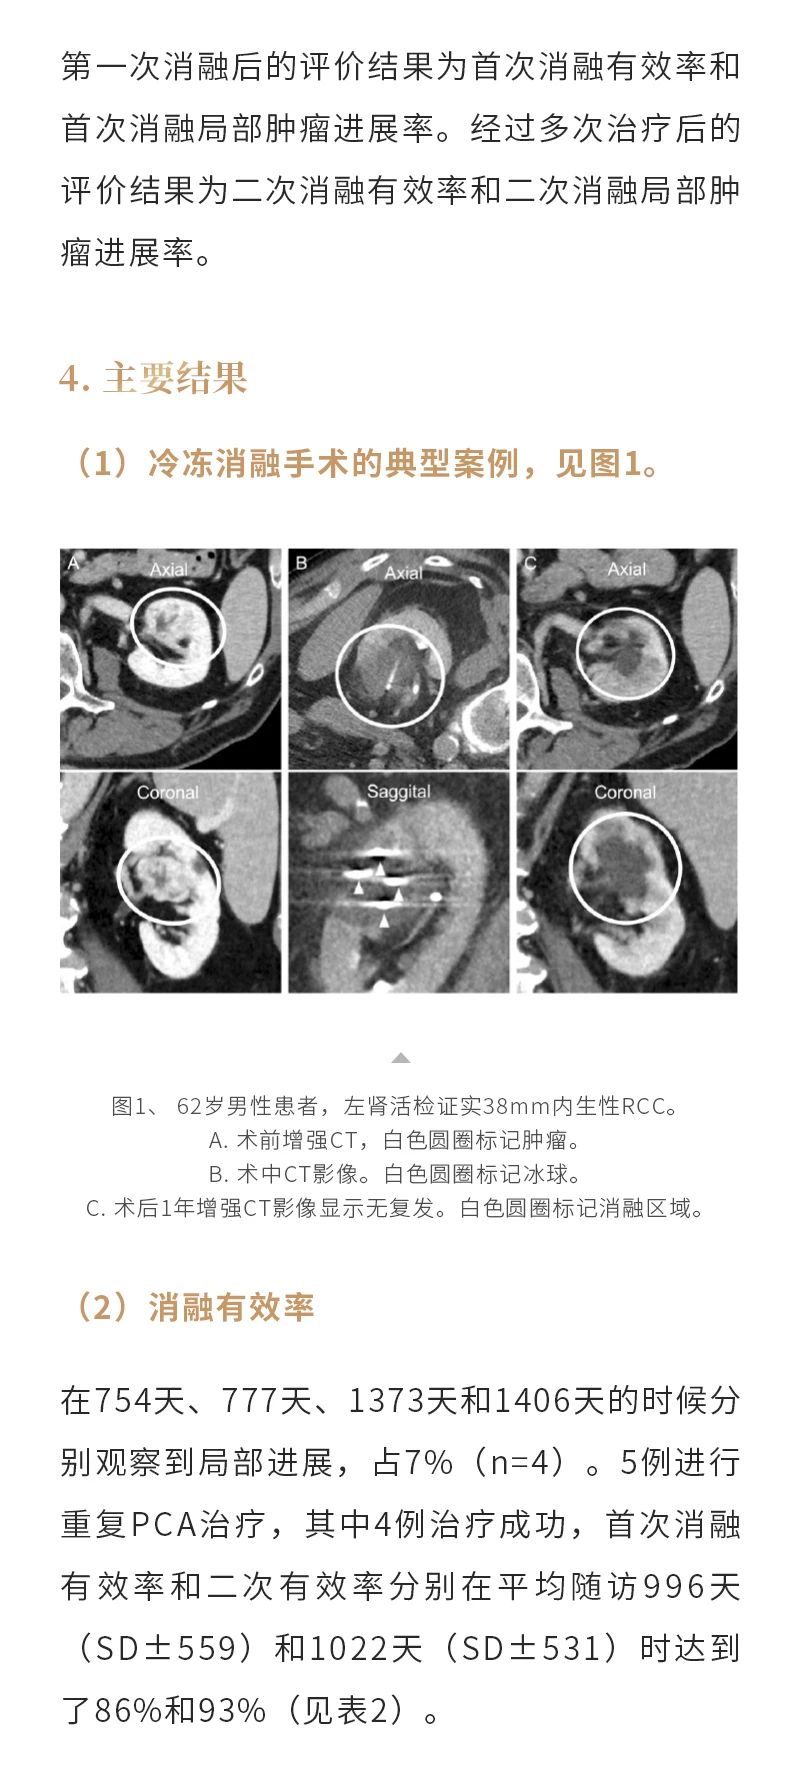

冷凍消融腎癌——【海杰亞科研資訊】第284期

發(fā)布時間:2024-10-18 | 作者:海杰亞 | 瀏覽次數(shù):711